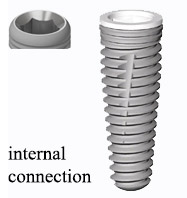

internal connection بدین معنی است که محل اتصال اباتمنت و فیکسچر (implant) که با اضلاع معمولا شش ضلعی است، قسمت انتهایى اباتمنت که برجستگى شش ضلعى دارد وارد حفره شش ضلعى که در ابتداى فیکسچر تهویه شده، مى شود و توسط پیچ محکم مىشود. در مینى ایمپلنت ها از این نوع اتصال معمولا استفاده نمىشود.